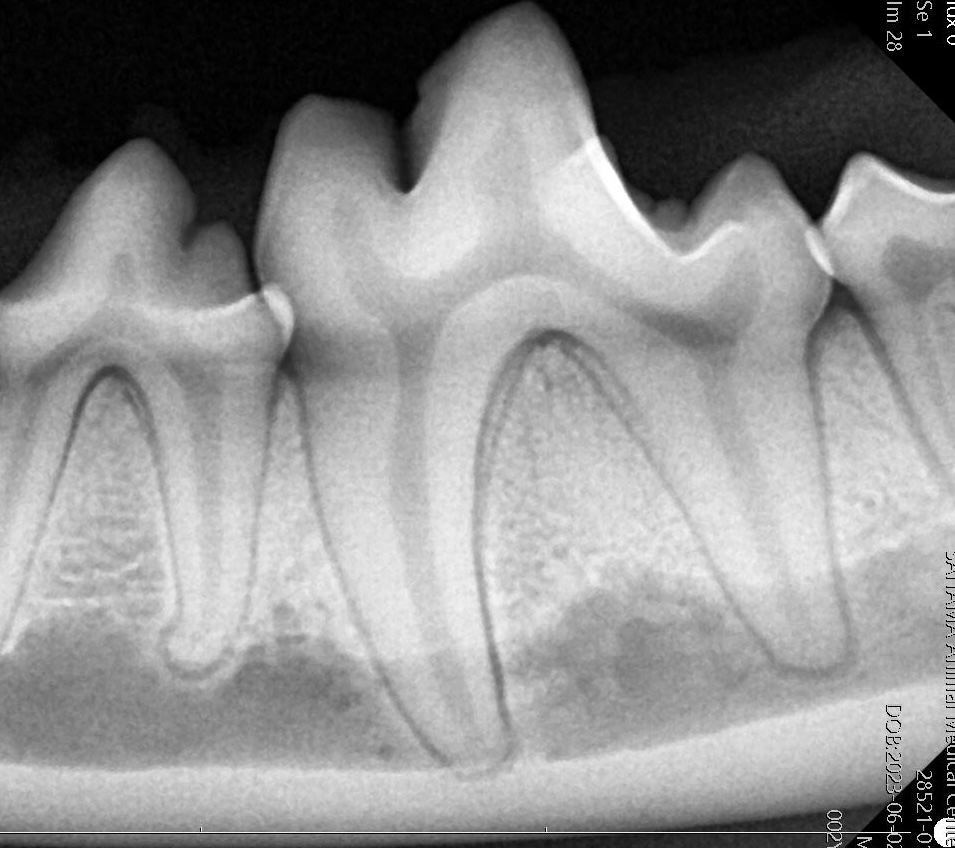

歯科用レントゲンによる精密診断

当院では、歯科診療専用のレントゲン装置を使用し、詳細な画像診断を行っています。一般的なレントゲンと比較して、歯や歯槽骨の状態をより鮮明に把握できるため、診断の精度向上につながります。これらの画像診断機器を活用し、病態を正確に評価したうえで最適な治療をご提案します。

正常な歯槽骨